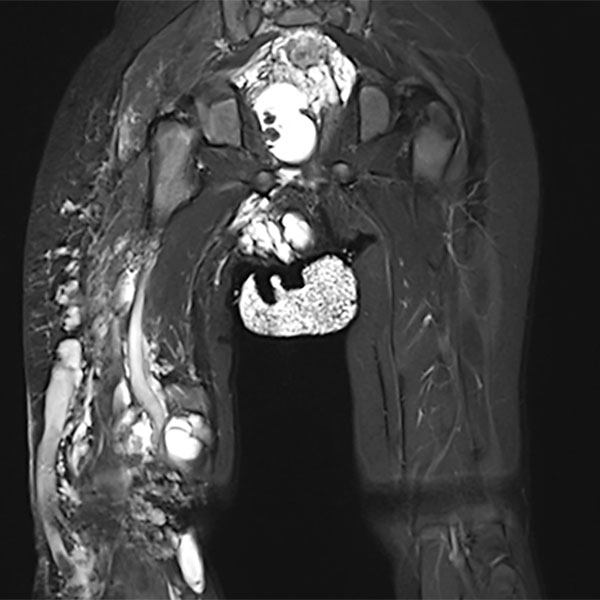

In der koronaren, T2-gewichteten, fettunterdrückten MRT des Beckens und der Oberschenkel zeigt sich die große Ausdehnung der Malformation. Mehrere Abschnitte mit mikro- und makrozystischen lymphatischen Malformationsanteilen. Dazu eine ausgedehnte venöse Malformation mit großer Marginalvene lateral am Oberschenkel rechts.

In der korrespondierenden axialen, T2-gewichteten, fettunterdrückten MRT des Beckens auf Höhe des Gesäßes zeigt sich die massive Ausdehnung vor allem auch der lymphatischen Malformation rechts gluteal. Zusätzlich abgebildet eine embryonal persistierende Vena sciatica im Sinne einer venösen Malformation.